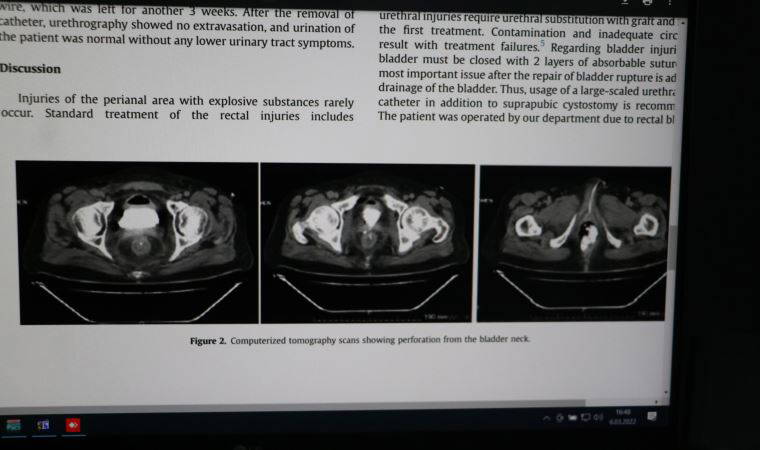

Bu sefer de daha önce görmediğimiz şekilde kendisine zarar vermiş, makatına torpil yerleştirmiş, fitilini de ateşleyerek patlatmış. Bu nedenle makatında büyük abdest bölgesi, mesane, prostatı, idrar yolları büyük zarar görmüş. Genel cerrahi bölümüyle birlikte çalışarak zarar gören organları büyük ölçüde onardık. Karnına da büyük abdestini yapabilmesi için torba takılmıştı. Yapılan tedavisinin ardından sağlıklı şekilde taburcu ettik. Böyle bir olayla ilk kez karşılaştığımız için makale olarak yabancı dilde yayınladık. Tıp literatüründe önemli dergi olan 'Urology Case Reports' a yayınlandı. Benim en çok atıf alan yayınlarımdan biri oldu. Vaka ilginç olduğu ve tedavi edilip, taburcu edildiği için tıp literatürüne de girdi" dedi.